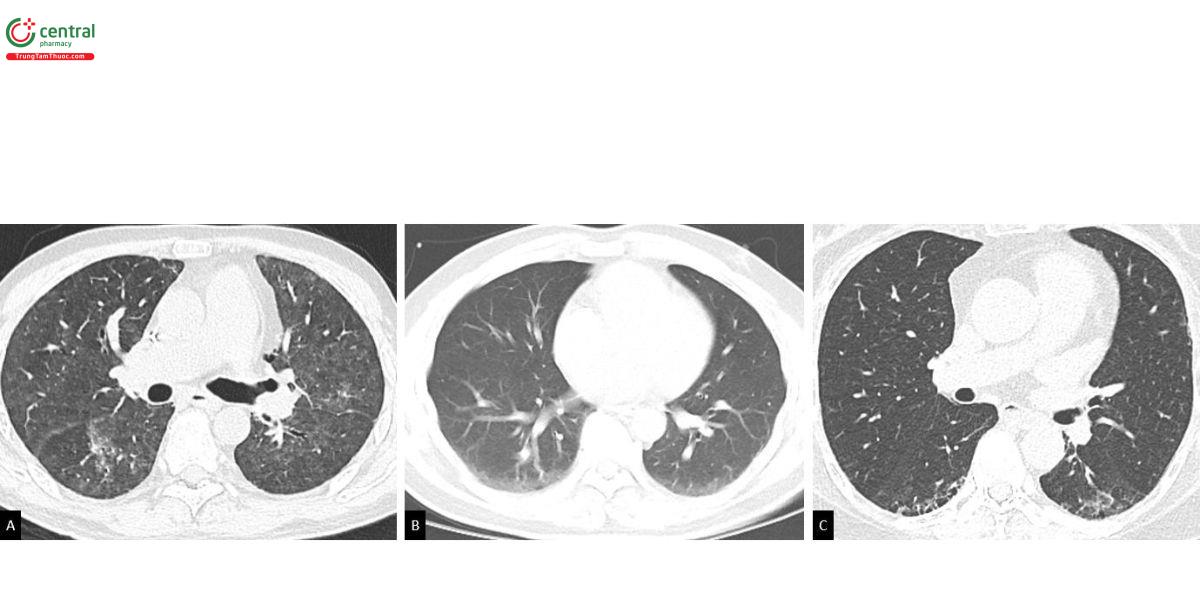

Việc phân loại các đặc điểm ILA sau đây có ý nghĩa tiên lượng: Nhóm một, tổn thương kính mờ và dạng lưới không phân bố ưu thế dưới màng phổi; Nhóm hai, tổn thương kính mờ và dạng lưới phân bố ưu thế dưới màng phổi nhưng không có bằng chứng xơ hóa; Và cuối cùng là dãn phế quản co kéo, biến dạng kiến trúc, tổ ong, kén khí gợi ý tiến trình xơ hóa [15, 16] (Hình 1). Kén khí (không bao gồm khí phế thũng), được định nghĩa là các hình sáng có thành không đều, rõ ràng, thường thấy ở những người hút thuốc lá. Các kén khí này có thể được phân biệt với khí thũng bởi có thành bao quanh rõ ràng và phân biệt với tổ ong bởi hình dạng không đều, kích thước khác nhau và không có ưu thế dưới màng phổi [17].